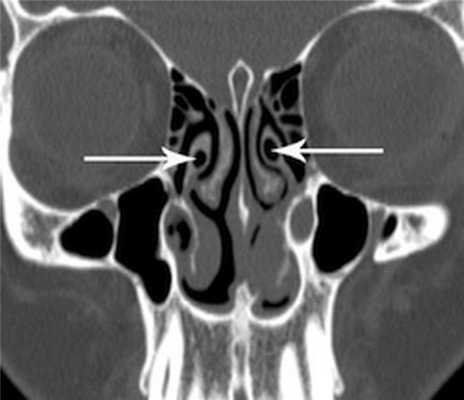

(Слева) На корональной КЛКТ в нижней части изображения визуализируется дно гипопластической ВП, находящееся выше дна носовых ямок. Утолщена слизистая оболочка обеих верхнечелюстных пазух. Решетчатые пазухи отсутствуют.

(Справа) На корональной КЛКТ определяется гипоплазия обеих ВП и аплазия левой решетчатой пазухи.